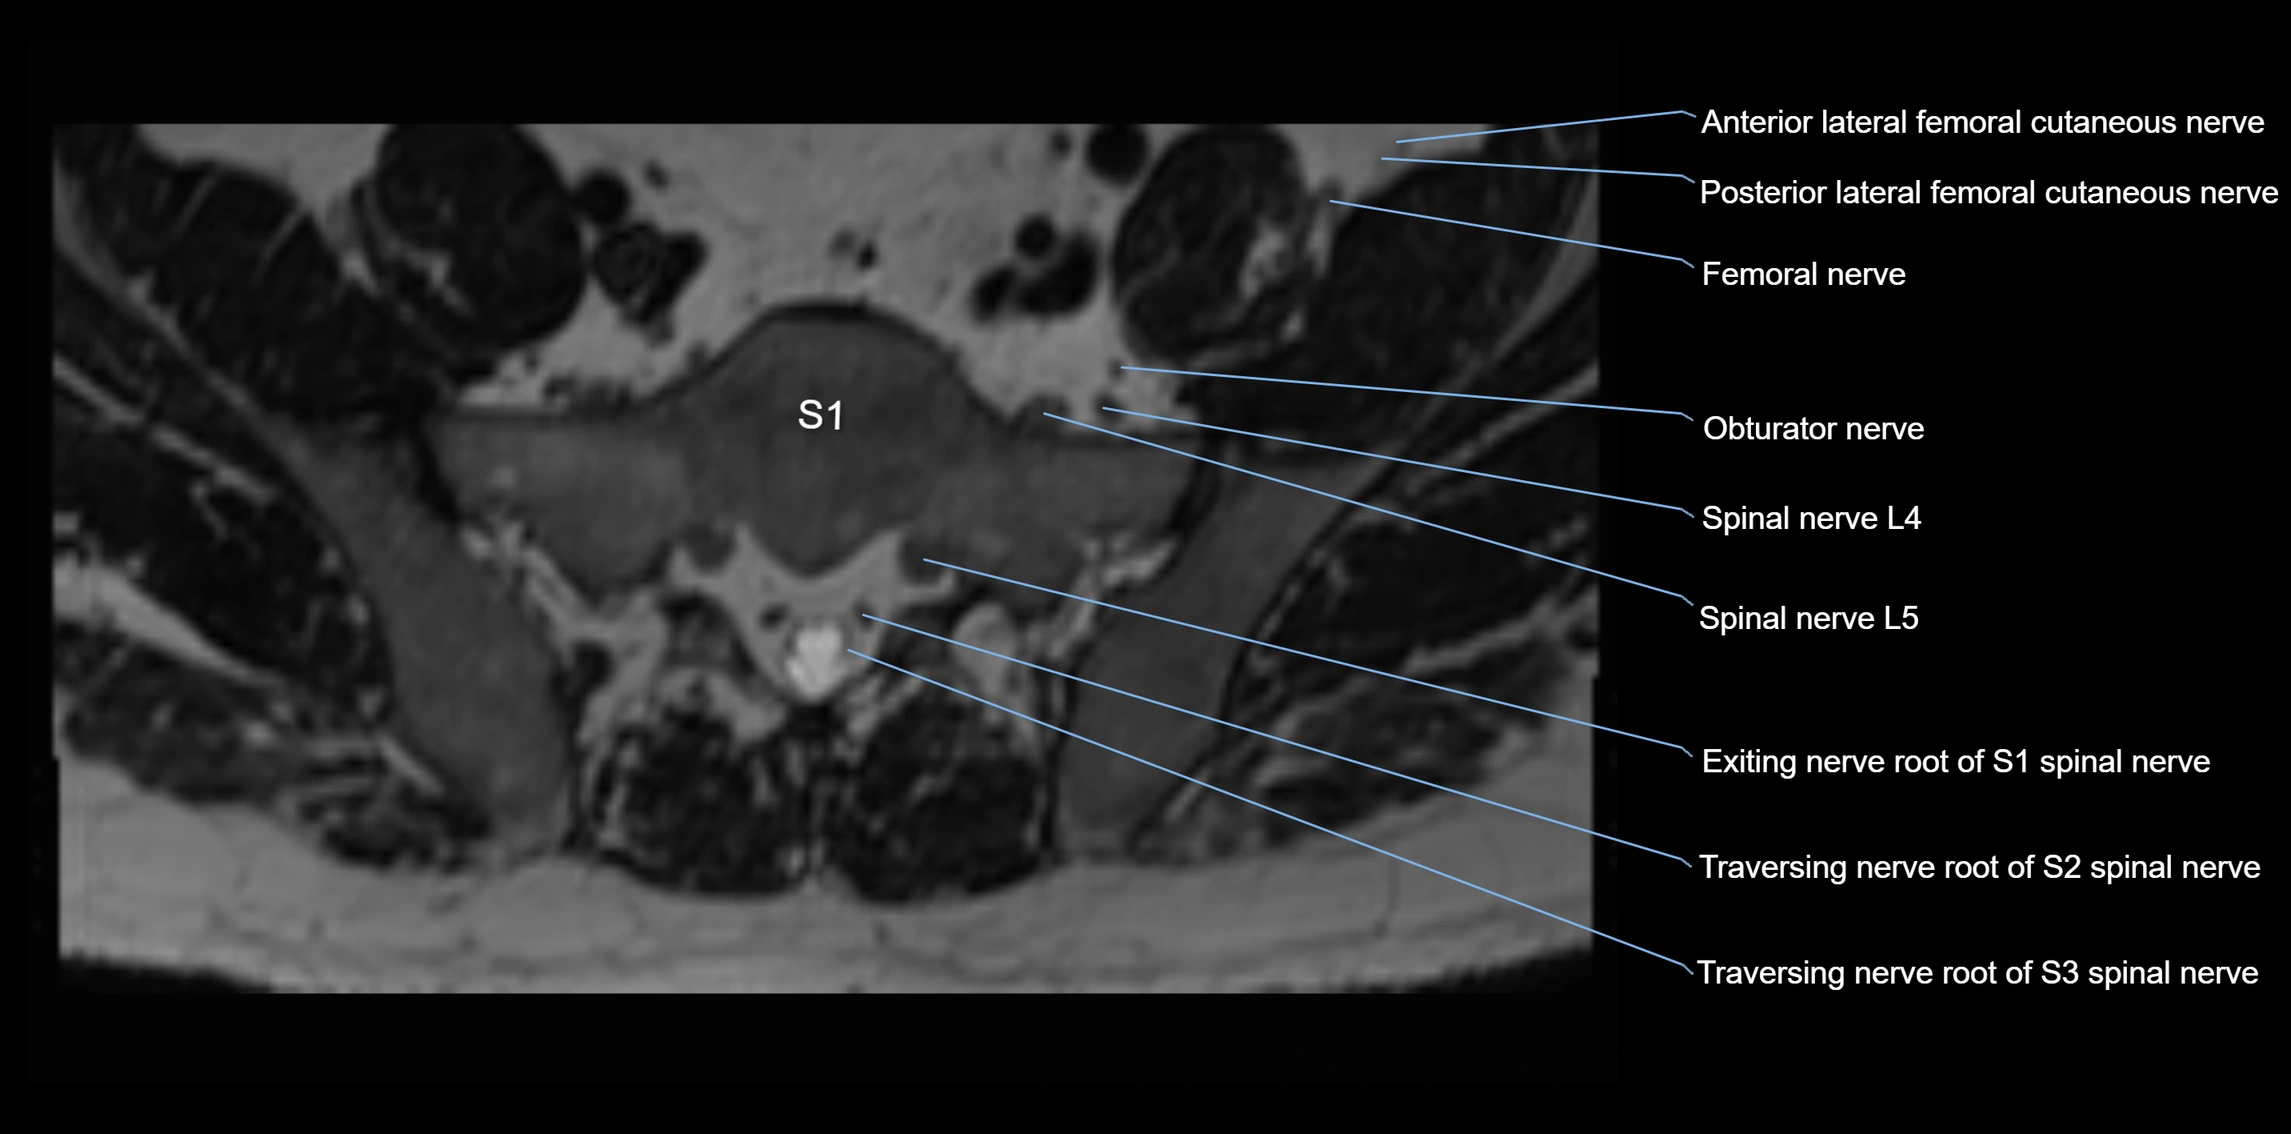

MRI image

image